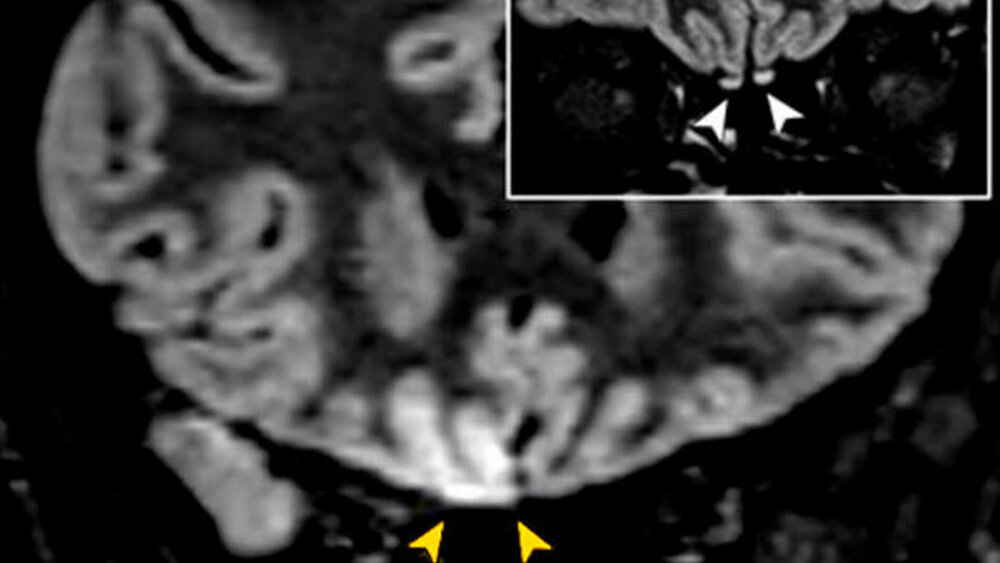

Ende Mai veröffentlichen Wissenschaftler aus Italien die Auswertung von MRT-Bildern einer 26-jährigen Patientin, die zunächst nur einen leichten Husten als Symptom aufwies und später ihren Geruchssinn verlor. Die Bilder zeigen Anomalien, welche den Verdacht nähren, dass das neuartige Coronavirus SARS-CoV-2 auch das Gehirn, hier vor allem den Kortex, befallen kann. Es besteht vermutlich ein Zusammenhang zwischen der Anosmie, also der eingeschränkten Geruchswahrnehmung, oder sogar des Verlustes des Geruchssinns und dem Virusbefall im Gehirn.

In der Studie erklären die Forscher: „Wir fanden den Nachweis einer in vivo-Hirnveränderung mittels MRT, die vermutlich auf SARS-CoV-2 zurückzuführen ist, und zeigen, dass Anosmie das vorherrschende Symptom bei COVID-19 darstellen kann.“ Bereits beim ersten SARS-Ausbruch 2001/2002 wurden neuronale Veränderungen bei Untersuchungen von Kleintieren festgestellt.

Weiter schlussfolgern die Wissenschaftler: „Basierend auf den MRT-Befunden (...) können wir mutmaßen, dass SARS-CoV-2 über den Riechweg in das Gehirn eindringen und eine olfaktorische Dysfunktion sensorineuralen Ursprungs verursachen könnte.“ Der verlorene Geruchssinn ist einer der neuronalen Symptome und lässt auf den Befall des Gehirns schließen. Für weitere Erkenntnisse zum Einfluss des Virus auf das Gehirn müsse nun weiterführend geforscht werden, so die Studienautoren.